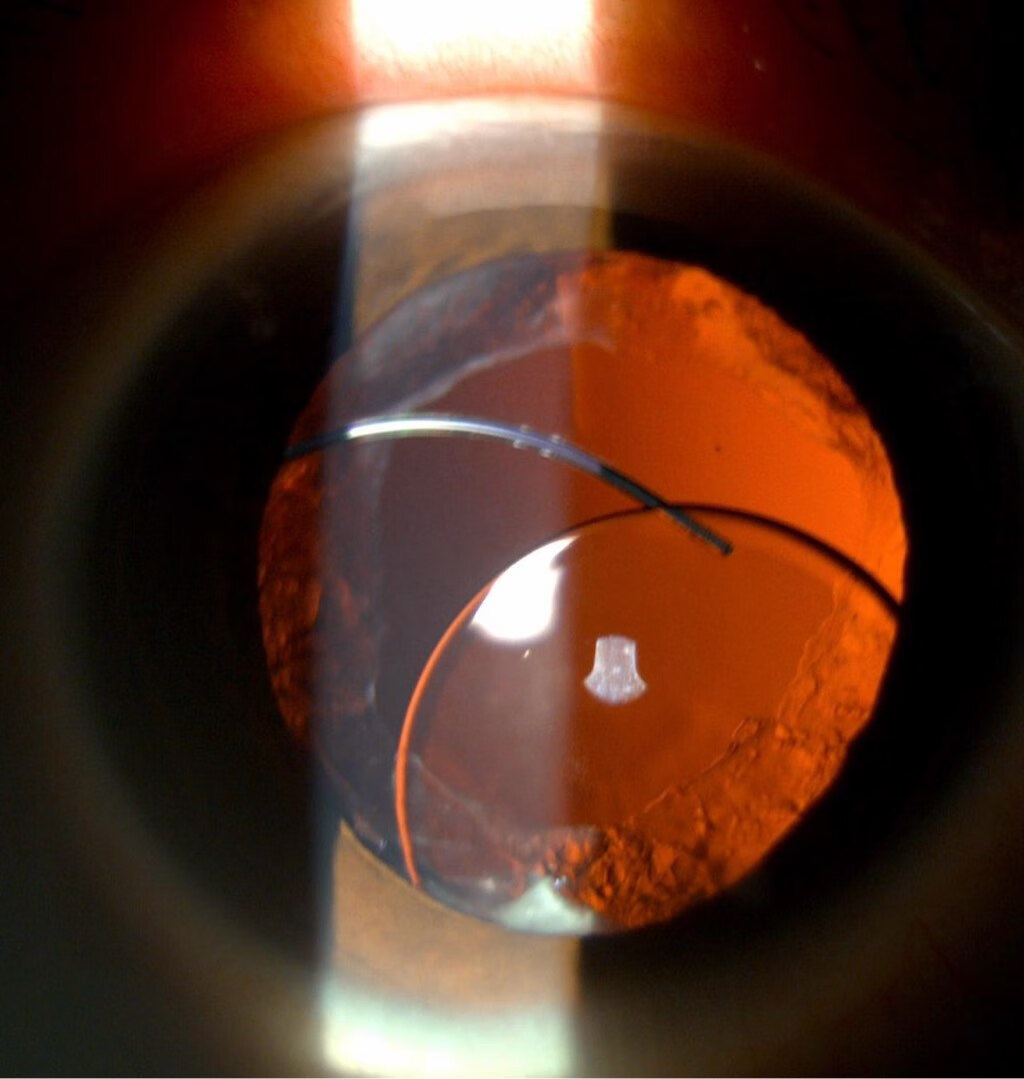

高度近视等视力问题。它就像一枚替代天然晶状体的“隐形镜片”,被精准植入眼球内,帮助患者重获清晰视力。然而,极少数情况下,这枚“镜片”可能发生移位,即“人工晶体脱位”。这种情况可能导致视力急剧下降甚至严重并发症,需要及时干预。

1. 裂隙灯显微镜:直接观察人工晶体位置及悬韧带状态。

复位术:通过微创手术将人工晶体调整至正确位置,并用缝线固定。

人工晶体置换:若原人工晶体损坏或无法固定,需植入新型晶体(如虹膜夹持型或巩膜固定型)。